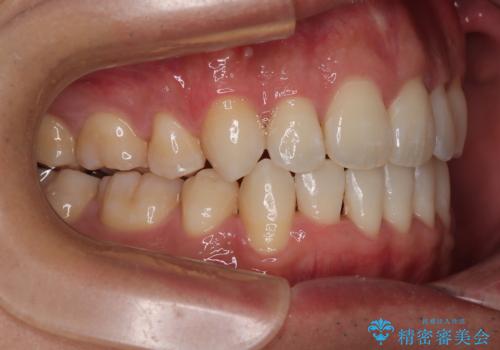

- 前歯のデコボコ(叢生)と、少し前に出た口元を気にされて来院された患者さまです。

診査の結果、上下顎ともに歯が並ぶスペースが不足しており、上下の前歯が噛み合わない**オープンバイト(開咬)**の状態でした。